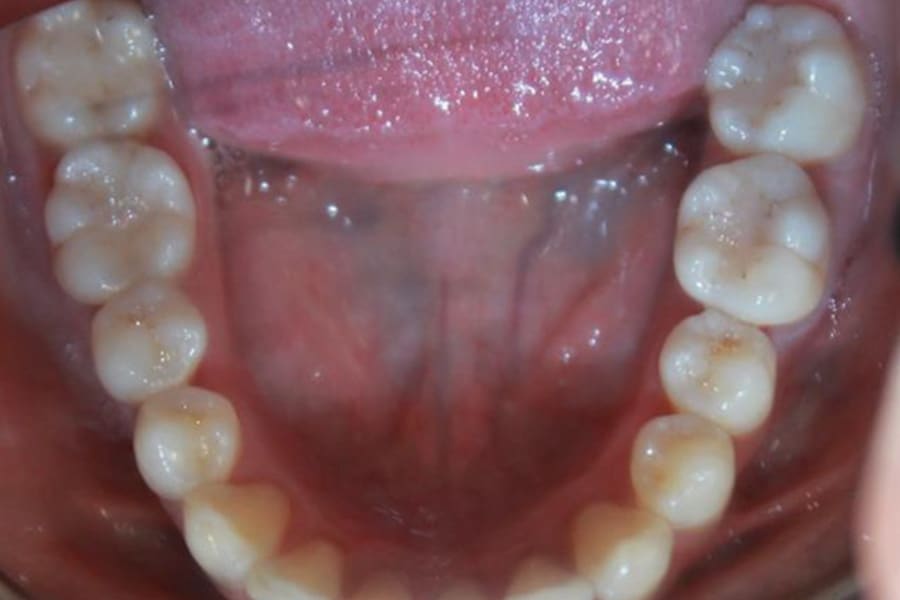

A 35-year-old woman presented with concerns of crowding, bruxism, and bite misalignment, which were associated with a class II malocclusion that would require a combination treatment of expansion, distalization, and molar derotation. ClearCorrect® aligner therapy (Straumann, clearcorrect.com) was selected as the primary modality, as the patient requested a non-invasive, esthetic treatment. The treatment plan was designed to be completed within 6 months of active aligner therapy. Class II elastics were prescribed, and the ClearCorrect FLEX case plan was chosen to allow for refinements, as needed. After comprehensive digital records were taken, the first set of aligners was delivered, engagers were bonded, and the patient was instructed to wear aligners on a 14-day cycle with full-time class II elastic wear. To enhance efficiency, more engagers were placed, including posterior attachments, to maximize control over molar distalization and anchorage. Interproximal reduction of 0.3 mm was performed in a few contacts at the initial appointment to facilitate space closure and alignment. Due to the complexity of the correction and the patient’s history of bruxism, a lower 3-3 bonded retainer was placed, and retainers were fabricated for both arches. The patient expressed a high level of satisfaction with the ClearCorrect aligner therapy, noting the comfort and esthetics of the aligners and the ability to achieve a fully corrected class II occlusion in just 6 months of treatment.